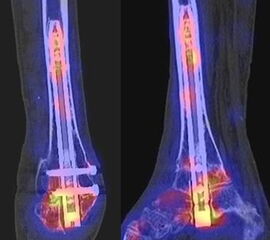

Beispiele für SPECT/CT-Untersuchungen nach OSG-TEP sind in den Abbildungen 6.1. bis 6.3. abgebildet.

Gurbani et al. evaluierten 37 Patienten mit schmerzhaften Sprunggelenkprothesen mit SPECT/CT und korrelierten die Ergebnisse mit klinischen und intraoperativen Befunden. Die SPECT/CT-Ergebnisse korrelierten zu 89,2 % (33/37 Pat.) mit der definitiven Diagnose. 28 Patienten wurden operativ revidiert und der Vergleich der SPECT/CT-Befunde mit den intraoperativen ergab eine Übereinstimmung von 92,9 % (26/28 Pat.). Die SPECT/CT identifizierte in den meisten Fällen aseptische Lockerungen (12/33 Pat.) und Impingement (11/33 Pat.). Seltenere Diagnosen waren Fehlstellungen (4/33 Pat.), Zystenbildungen (2/33 Pat.), subtalare Arthrosen (2/33 Pat.) und Infektionen (2/33 Pat.) 51.

Die Autoren beschreiben einen Fall, der neben einem Fokus am lateralen Malleolus auch eine starke flächige Anreicherung am talaren Prothesen-Knochen-Interface 17 Monate nach TEP-Implantation aufwies, so dass neben dem Verdacht auf ein laterales Impingement auch der Verdacht auf eine Lockerung der talaren Prothesenkomponente geäußert wurde. Intraoperativ bestätigte sich die Lockerung der talaren Prothesenkomponente nicht, sondern nur das laterale Impingement, welches mittels Debridement erfolgreich therapiert wurde 51. Da der Pat. bereits vor der TEP-Implantation eine Triple-Arthrodese erhalten hatte (welche im SPECT/CT unauffällig war), kann eine solche flächige Mehrspeicherung auch als weitgehend asymptomatische Stressreaktion gewertet werden.

Mertens et al. 52 berichten unter Anwendung eines standardisierten Auswerte-Schemas über eine Treffsicherheit von 96 % (Sensitivität 100 %, Spezifität 80 %) des SPECT/CT zur Diagnose der Ursachen für eine schmerzhafte Sprunggelenkprothese (n=24). Der SPECT/CT-Befund führte in 86 % zu einer spezifischen Therapie, welche in 83 % der Fälle zum Therapieerfolg führte.

Eine Analyse von Mason et al. 53 von 14 Patienten mit schmerzhaften Sprunggelenksprothesen, welche mittels SPECT/CT untersucht wurden, fanden in 13/14 Patienten ein SPECT/CT-Korrelat für die Beschwerden, wobei bei 12 Patienten der Fokus talar medial lokalisiert war. 8 Patienten wurden operativ revidiert und der Fokus entsprach einer verminderten bzw. fehlenden ossären Integration der talaren Prothesen-Komponente.